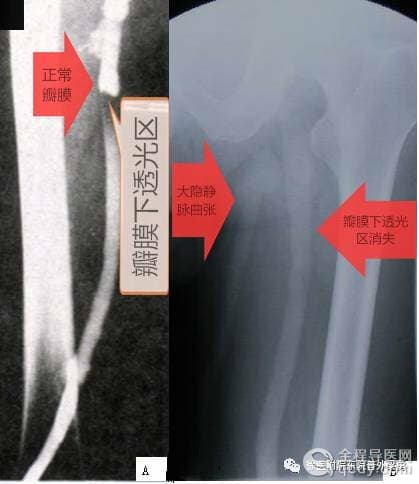

表现为深静脉全程显影,通畅。静脉瓣影清晰,瓣窦对称突出呈竹节状。Valsalva实验显示股静脉瓣关闭,瓣膜下透亮区,无造影剂逆流,无交通静脉逆流及其引起的浅静脉显影,股静脉瓣膜下宽径<14mm, 腘静脉宽径<12mm。

A 正常瓣膜 B 瓣膜功能不全

深静脉扩张,宽径>14mm,瓣膜稀少且模糊,丧失竹节状呈直筒状外观。Valsalva实验显影的静脉向远端逆流,瓣膜下无透光带,浅静脉和交通静脉迂曲扩张。